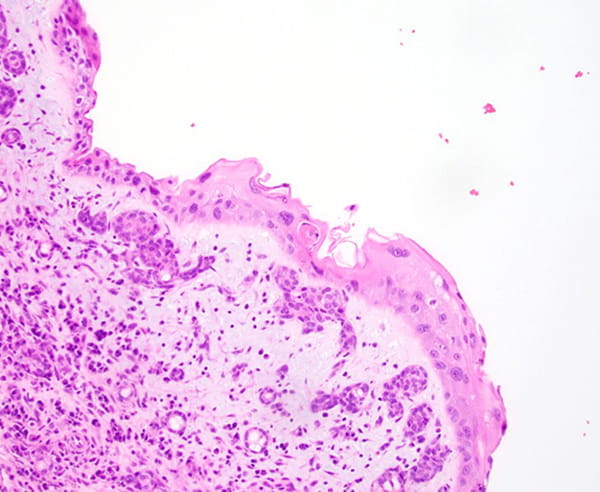

The tumor predominantly grows in the submucosal areas, forming cribriform nests, ductal structures, trabecular arrangements, or solid sheets. The tumor cells are basaloid with scant cytoplasm. Focal areas of squamous differentiation, characterized by eosinophilic cytoplasm, are observed. The overlying squamous mucosa exhibits high-grade dysplasia.